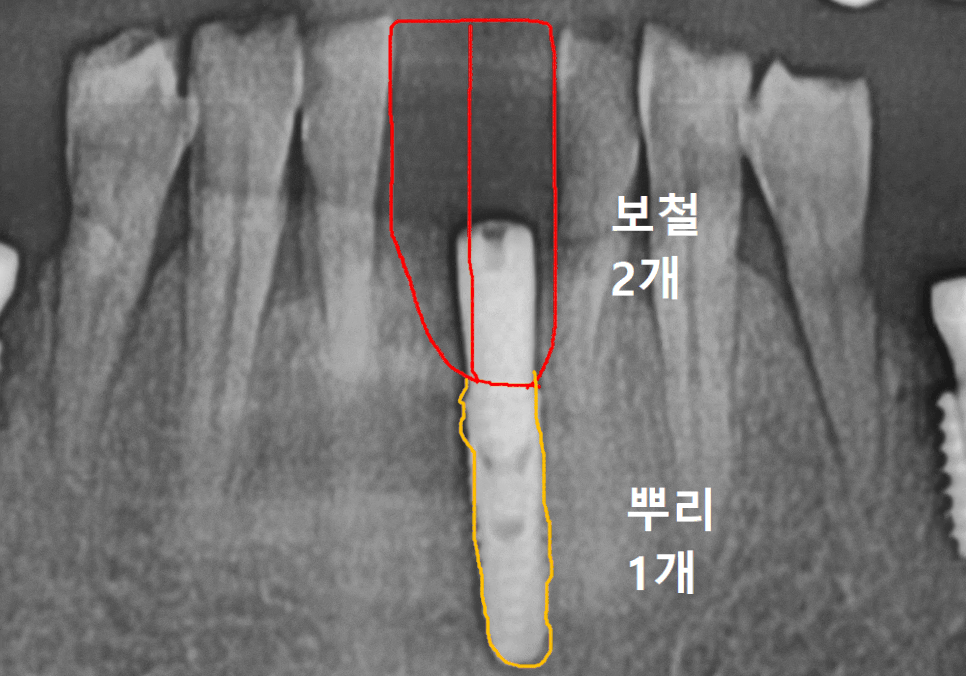

캔틸레버는 쉽게 말해

임플란트 1개를 지지대로 세우고,

그 위에 치아 2개 형태의

보철을 연결하는 방식입니다.

즉, 임플란트 뿌리는 1개이고

그 위에 올라가는 머리는 2개가

같이 올라가는 형태인데요,

임플란트 1개로 2개를 버틴다면, 지지대는 더 든든해야 합니다.

강동구 임플란트 가격 줄이는 방법

다만 여기서 중요한

포인트가 있습니다.

임플란트를 1개만 심고

크라운을 2개로 연결하는 구조라면,

말 그대로 임플란트 뿌리(픽스처) 1개가

보철 2개를 지지해야 합니다.

그래서 이번 케이스는

일반적인 앞니용처럼

얇은 직경의 픽스처를 쓰기보다는,

직경이 더 큰 임플란트를 사용

가능한 범위 안에서

조금 더 직경이 넓은 픽스처로

계획해 안정성을 확보했습니다.

'개수는 줄이되, 지지대는 더 든든하게'

이런 방향으로 이해하시면 됩니다. ^^